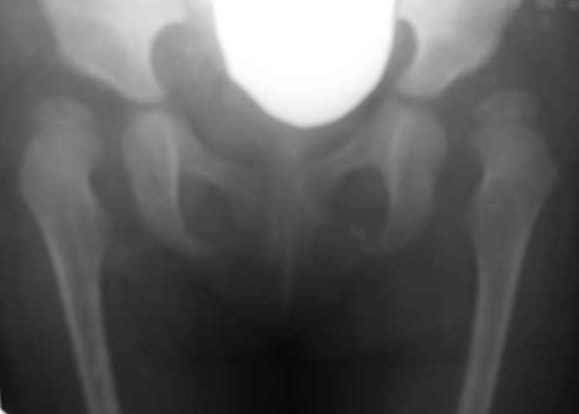

Дисплазия тазобедренного сустава у девочки 2х лет.

Из анамнеза: в 10 месячном возрасте поставлен диагноз врожденного вывиха бедер. Лечилась консервативно на данный момент. Рг-картина неудовлетворительная. Посоветуйте, пожалуйста тактику оперативного лечения.

Na snimke mild dysplasia, hughe sleva, no est isprava.

V2,4 goda nelsya prosto vpravlyat bez ukorochenia bedra-inache poluchite AVN.Net nadobnosti delat varus-Neck shaft angle uetih detei mormalnyi.Vvashem sluchae mne kaghetsya net smysla delat open reduction-po moemu idealno budet proizbesti -shortening,derotation 20-30 dedrees+Dega/Salter( po vashemu vyboru).posylau vam statyu po teme.